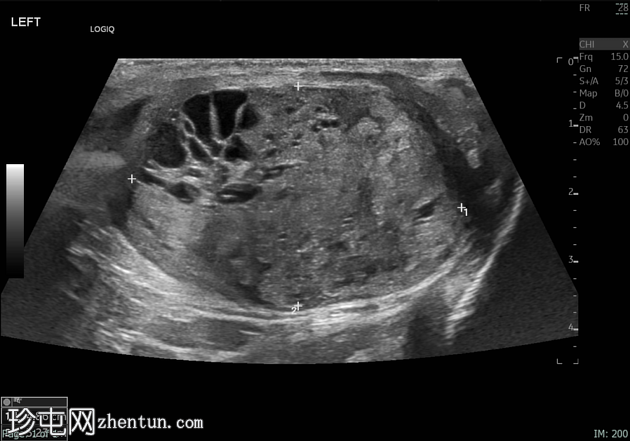

纵切面

/ 横切面

左侧睾丸肿大,体积约56 mL,可见弥漫性微结石,以及三个内部等回声病灶,伴囊性变、微钙化和明显血流信号,最大病灶大小约4.8 x 3.2 cm。

未见腹主动脉旁或髂淋巴结肿大。